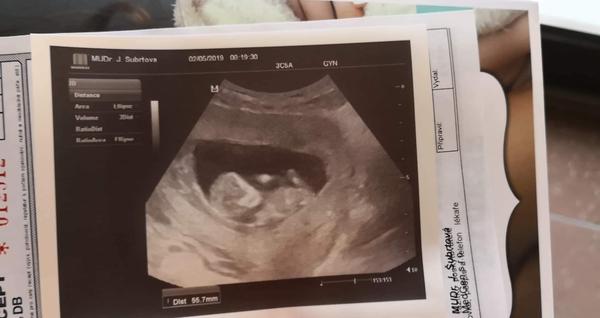

Termín porodu listopad/prosinec 2019

Ahoj holky. Pojďte se přidat všechny co budeme mít předvánoční nebo vánoční krásné dárečky 😍 přeji všem aby bylo vše v pořádku. Já jsem své // čárky našla 27.3. Doma už máme 22 měsíční holcicku.

Ahoj 🙋. Já našla svoje // 24.4,přítel to dostal k svátku ten den. Termín máme 29. 12.2019.

Ahoj holky, ta jsem se po X letech konečně poprvé zaregistrovala vždy jsem jen projížděl diskuze jako neaktivní člen, tak mam radost ze mohu byt konečně mezi Vami❤️jinak my mame termín 25.11-1.12 a jsme 11tt včera byla kontrola a odebrani krve na prvotrimestrální screening ktery nas čeká příští pátek, doktorka mi dokonce rekla i pohlaví což me trochu zarazilo, přiznám se ze jsem zadržovala slzy jelikoz jsem si přála vysněnou holčičku a na ultrz. Byl zvoneček 😄😄ale dnes jsem uz happy protože malej (4)bude mít bráchu a je to pro něj to nejlepší co může být ❤️